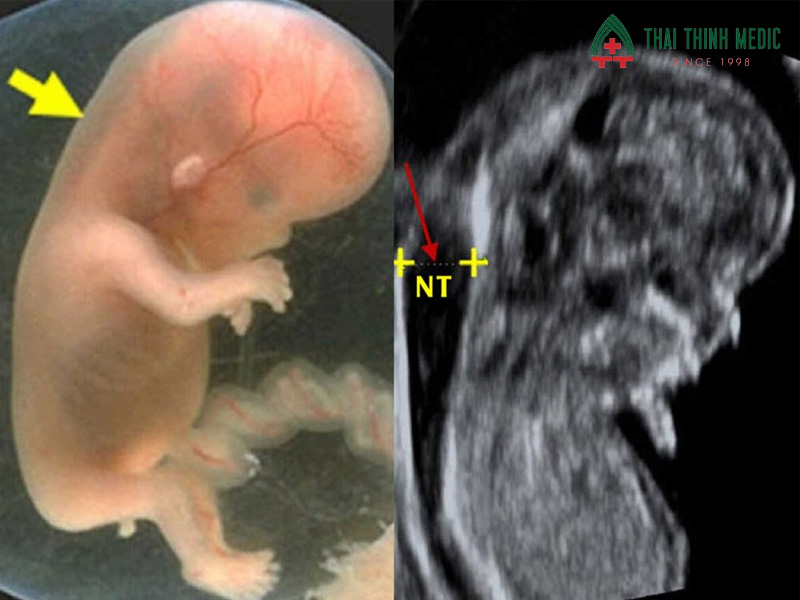

Độ mờ da gáy

Độ mờ da gáy (Nuchal Translucency – NT) là lớp dịch phía sau gáy thai nhi được đo trong tuần 11–13. Đây là chỉ số quan trọng để sàng lọc nguy cơ dị tật nhiễm sắc thể, đặc biệt là hội chứng Down. Chỉ số NT > 3 mm có thể là dấu hiệu cần làm thêm xét nghiệm NIPT hoặc chọc ối để đánh giá chính xác.